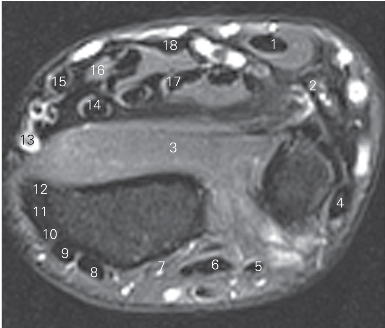

图4-37 经前臂下份的横断层MR T2WI FS

1 尺侧腕屈肌腱 tendon of flexor carpi ulnaris 2 尺神经 ulnar nerve

3 旋前方肌 pronator quadratus

4 尺侧腕伸肌腱 tendon of extensor carpi ulnaris

5 小指伸肌腱 tendon of extensor digiti minimi

6 指伸肌腱 tendon of extensor digitorum

7 示指伸肌 extensor indicis 8 拇长伸肌 extensor pollicis longus

9 桡侧腕短伸腱 tendon of extensor carpi radialis brevis

10 桡侧腕长伸肌 extensor carpi radialis longus

11 拇短伸肌 extensor pollicis brevis

12 拇长展肌 abductor pollicis longus 13 桡动脉 radial artery

14 拇长屈肌腱 tendon of flexor pouicis longus

15 桡侧腕屈肌 flexor carpi radialis 16 正中神经 median nerve

17 指深屈肌 flexor digitorum profundus

18 指浅屈肌 flexor digitorum superficialis